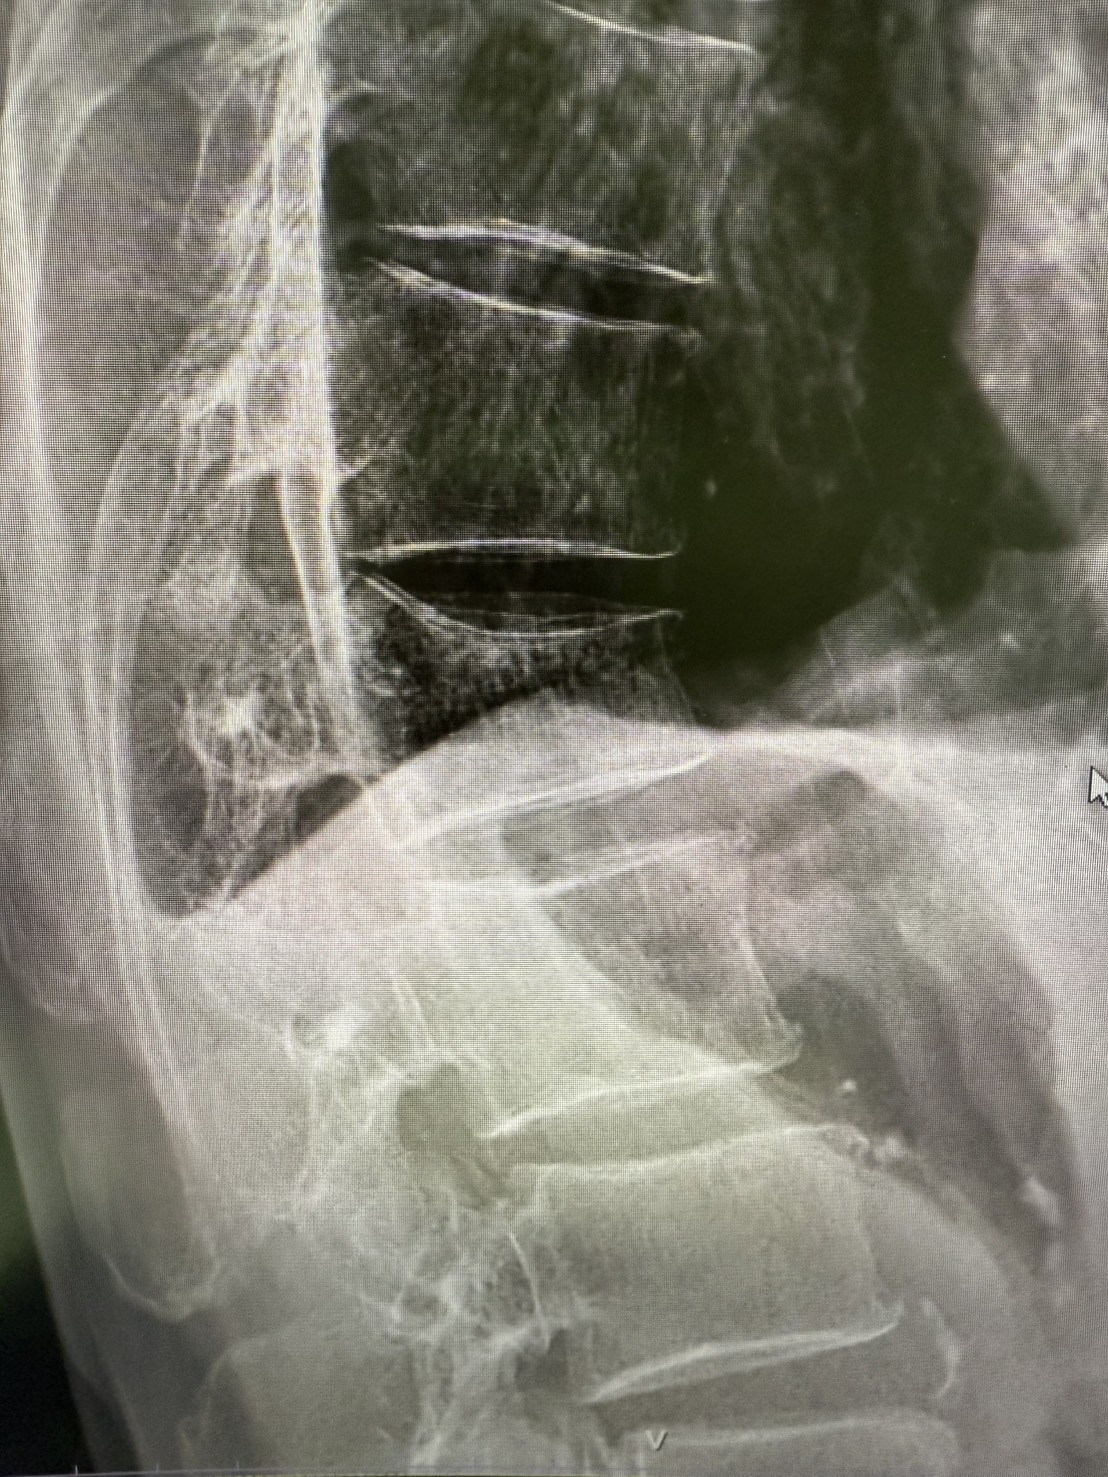

การรักษาโรคกระดูกสันหลังเสื่อมกดทับเส้นประสาทโดยไม่ต้องผ่าตัด

โรคกระดูกสันหลังเสื่อมกดทับเส้นประสาท หรือที่เรียกกันว่า “กระดูกทับเส้น”...